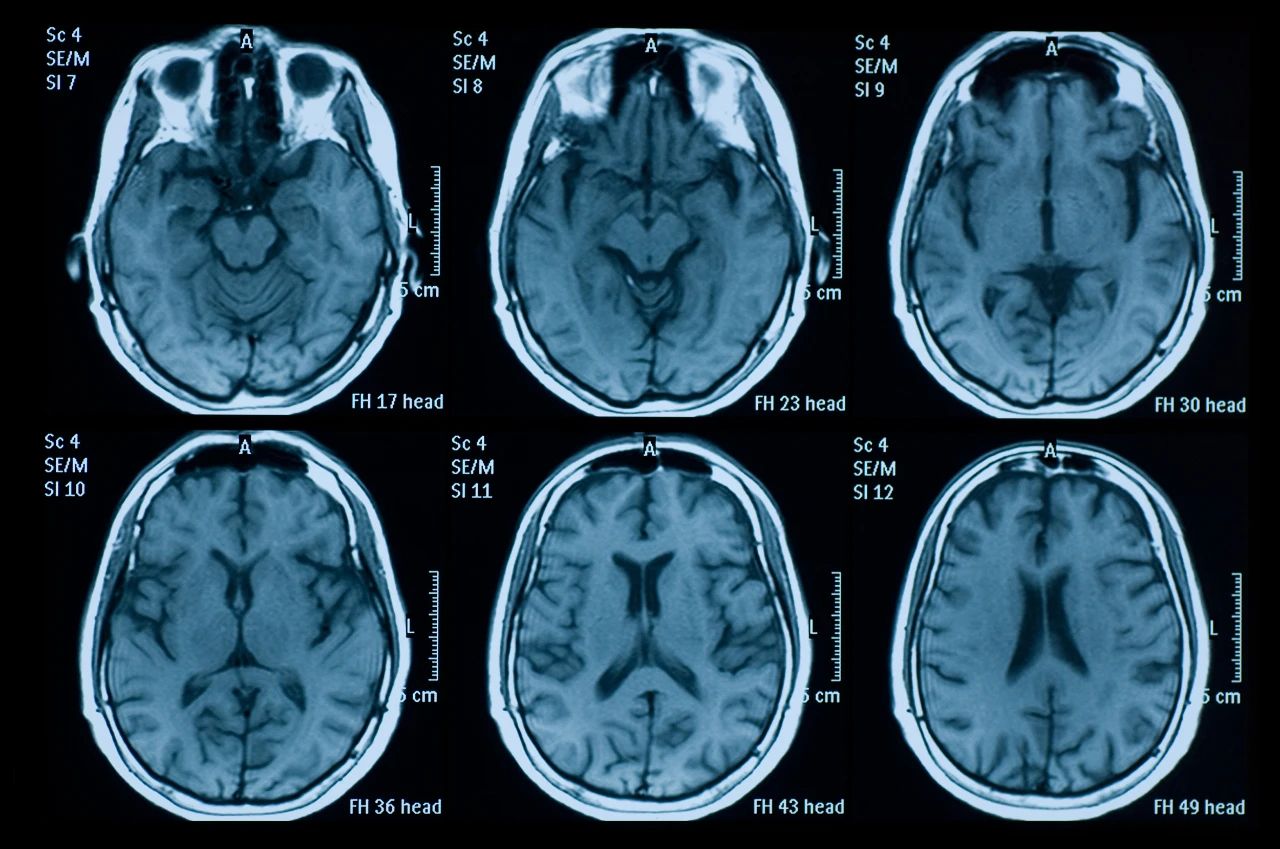

什么是創(chuàng )傷性腦損傷?

頭部受傷是頭部受到撞擊。它可能是輕微的,導致小腫塊或瘀傷,也可能更嚴重,導致腦損傷,如腦震蕩或腦出血。

即使您看不到頭部受傷也可能很?chē)乐?。它們可能導致永久性殘疾或損傷,甚至死亡。更嚴重的頭部受傷總是需要去看醫生。